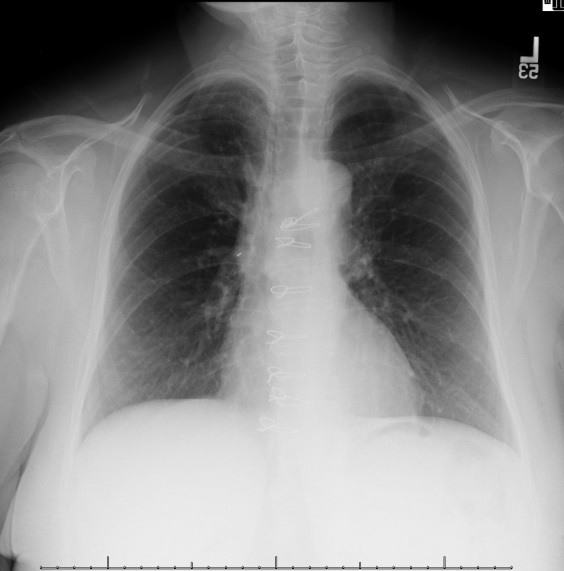

A 58-year-old woman presented with a symptomatic, massive pericardial effusion. Due to shortness of breath for over three months, she underwent percutaneous pericardial drainage (Fig. 1). She had no other significant medical problems.

1.5 liters of serous, odorless fluid was removed and the echo appearance normalized, showing only trace pericardial fluid and a well-preserved ejection fraction. However, within four weeks the effusion re-accumulated as shown in the CXR (Fig.2) and echo showed early tamponade.